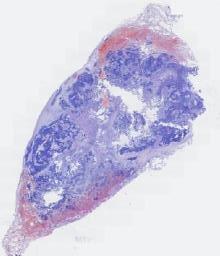

临床资料: 女,37岁,发热(体温高达42℃)、乏力、纳差2天入院。多种病原体检测均阴性。既往体检,无肿瘤病史。外院CT:右肺下叶占位。气管镜下见:右肺下叶段支气管新生物阻塞管腔,经内镜下肿瘤治疗,治疗后右肺下叶基底段支气管开口正常,右下叶背段开口狭窄,部分新生物阻塞管腔,远端无法进境。

大体所见: 我院胸腔镜下右肺下叶切除,大体见:灰黄色肿瘤,最大径2.5cm,实性质软,部分位于支气管腔内。